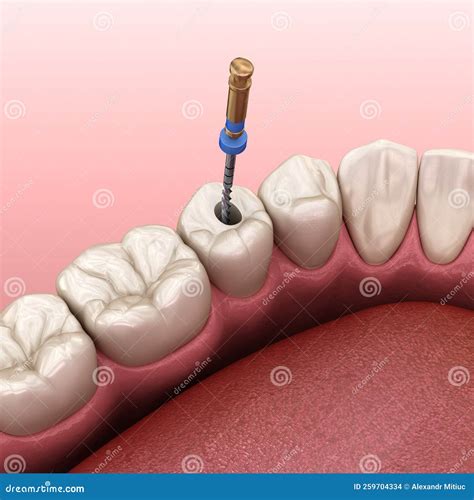

• Root canal treatment: Removing the infected pulp from the tooth and sealing the root canal to prevent further infection.